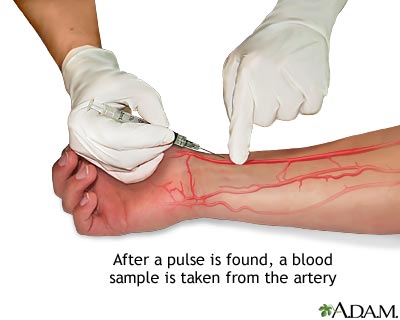

- Importance of blood tests & blood groupings e.g. HIV/AIDS cell anemia